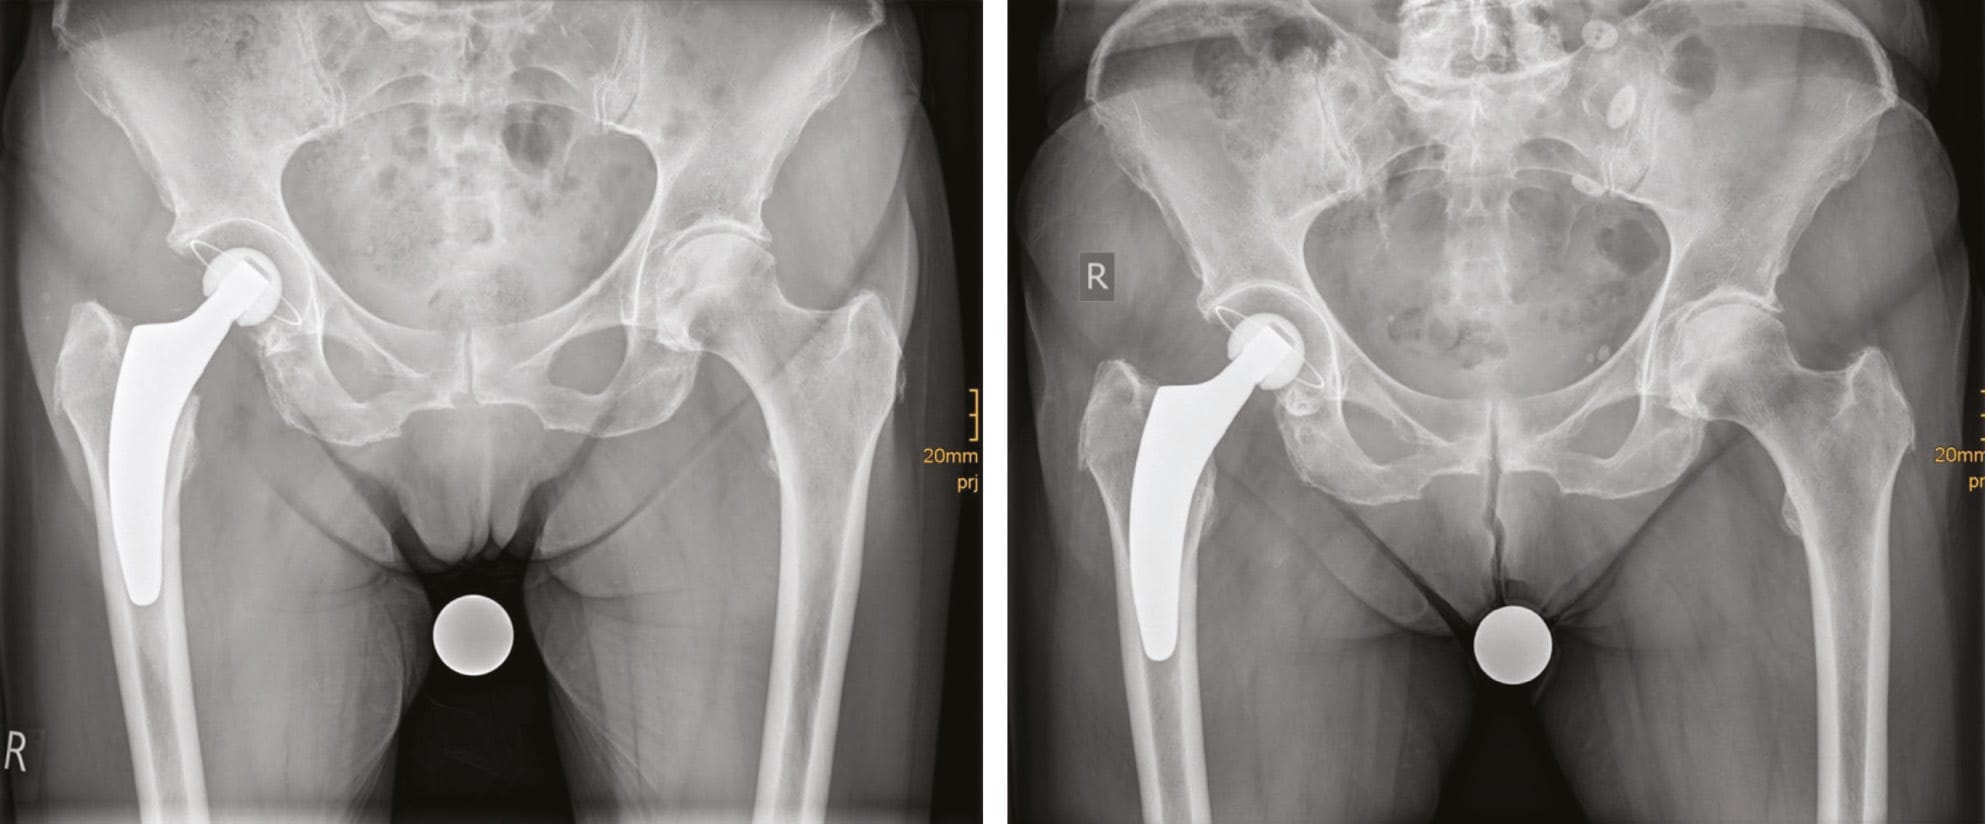

Hemiarthroplasty (HA) with 37% is still widely used. However, 57% of our patients obtain a THA. Cemented fixation is necessary in most cases due to bone quality, intraoperative cortical ring structure or known osteoporosis in the patient history. In active patients with good bone quality, femoral Dorr type A or B, intact cortical ring cementless fixation is possible. If cementless fixation is considered short stem fixation is possible and our favoured method. Straight cementless stems are rarely used. Our clinical and radiographic results using cementless short stems so far are very promising (Figure 4). Clinical results in these selected cases are excellent and complication rates are low. Currently a clinical and radiographic study is under process and will be finished by 2019.

Since 2017 the use of dual mobility cups have become more popular in our department. In cases with a higher risk of dislocation and signs and symptoms of OA it is our favoured method. Thus numbers with this procedure will probably rise in the near future. In 2018 10% of our cases received a dual mobility cup. Maybe the “dual mobility concept” will replace the “hemiarthroplasty concept” in the future as the current literature reveals excellent clinical results (Kim et al. 2018, Tabori-Jensen et al. 2018) in the use of dual mobility in femoral neck fractures. Thus further data and experiences are necessary.